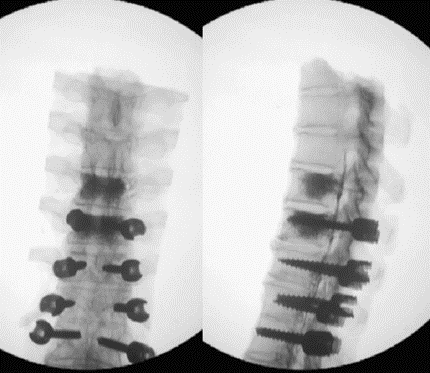

(4)固定棒选择

图8-11 相关文献表明,钴铬合金可提高固定强度及融合率,防止断棒,但也增加了PJK的发生率

图12 CBT+TT+多棒固定

CBT+TT+多棒固定